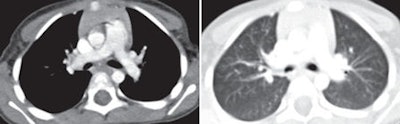

| Above images show a 3-year-old boy weighing 14.7 kg (32.3 lb) imaged with 120 kVp and measured noise of 9.6 HU. Images below are of a 4-year-old boy weighing 14.1 kg (31 lb) imaged with 80 kVp and measured noise of 11.3 HU. All transverse CT images with mediastinal and lung windows were rated as having good image quality. Images courtesy of the American Journal of Roentgenology. |